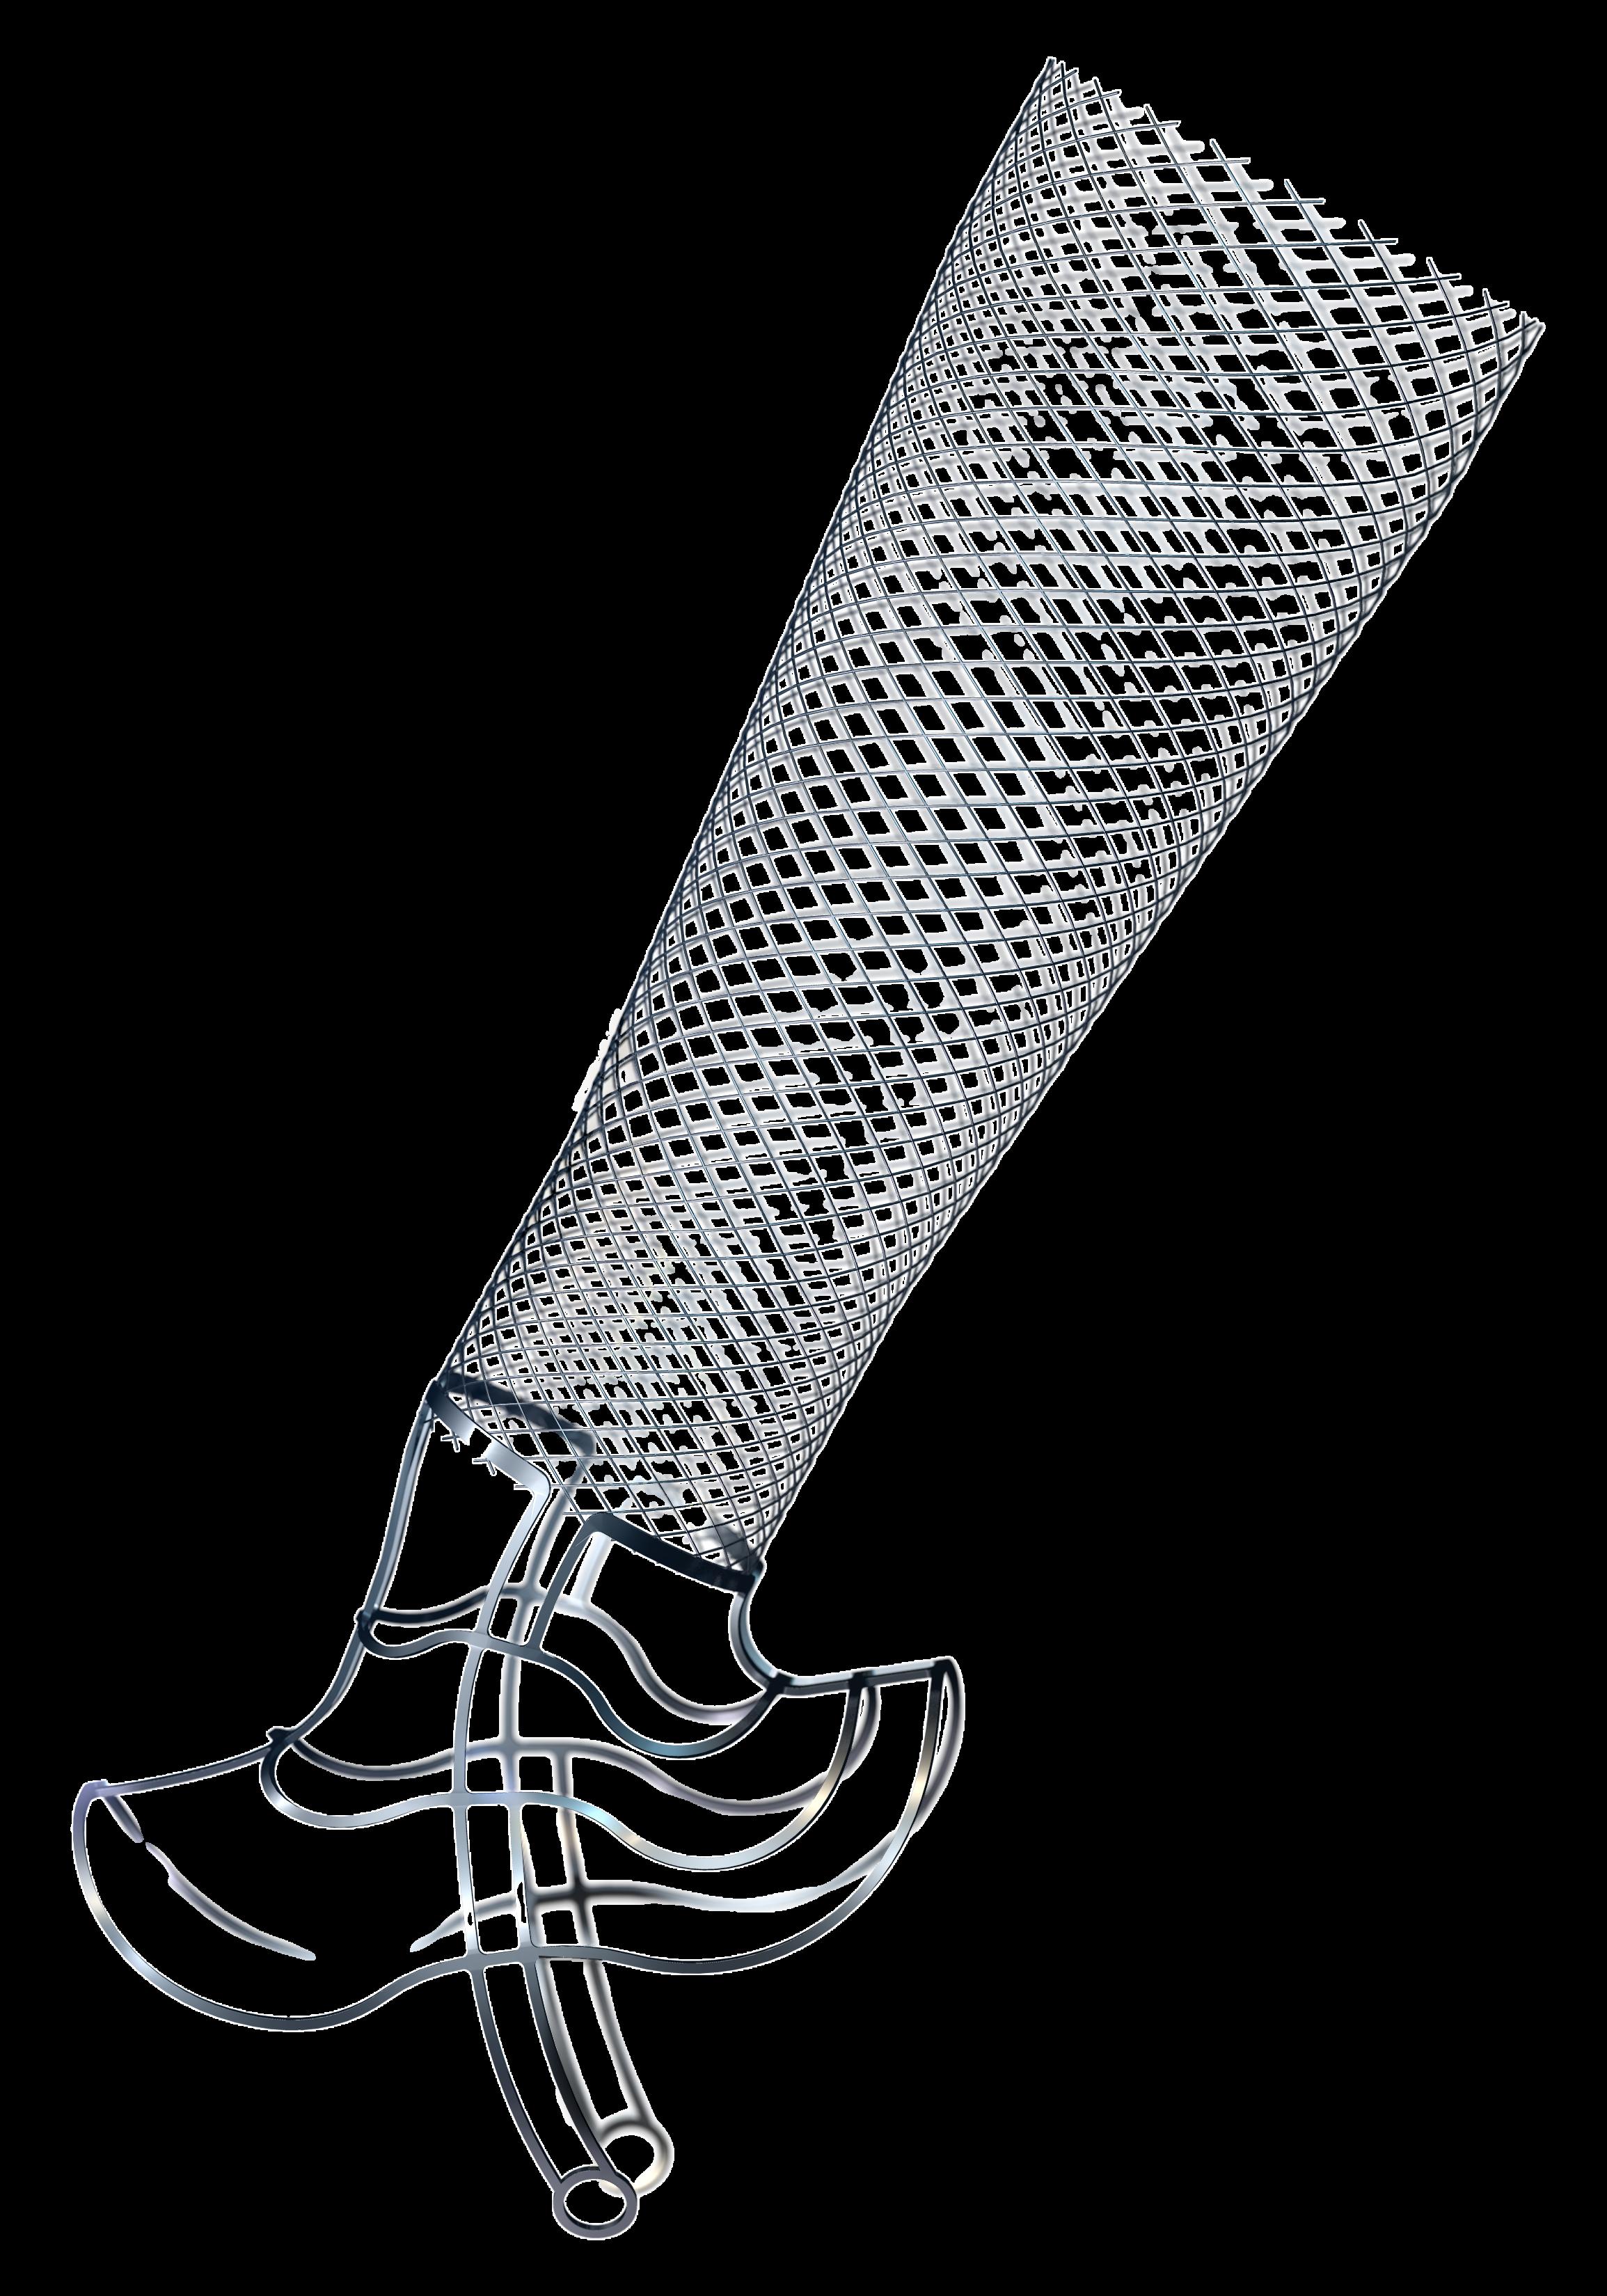

Positive six-month findings from the randomised arteriovenous (AV) fistula arm of Merit Medical’s Wrapsody arteriovenous access efficacy (WAVE) pivotal trial have been revealed. The data were shown at the Cardiovascular and Interventional Radiological Society of Europe (CIRSE) annual congress (14–18 September, Lisbon, Portugal) during a FIRST@ CIRSE presentation. Wrapsody is a cell-impermeable endoprosthesis which is intended to extend long-term vessel patency in dialysis patients.

For more on this story go to page 22.

outcomes of a randomised clinical trial of endothermal ablation versus conventional surgery for great saphenous varicose veins; and a report of Merit Medical’s Wrapsody WAVE trial that demonstrated superior patency versus standard of care in arteriovenous (AV) fistula patients.